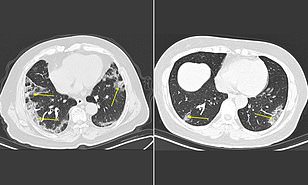

CT scans may help doctors diagnose coronavirus patients four DAYS faster than the CDC's test by revealing lung damage

Very interesting and thanks for sharing as I have wanted to see what the "ground glass" lesions we had heard about before looked like.

From the link above, this part is what I found to be a good summary. Toward the bottom of what I cut out, they can use the CT scan technique pretty reliably when done 3-5 days after onset of symptoms:

"Thirty-six patients received scans zero to two days after reporting symptoms and more than half showed no evidence of lung disease.

The team says this is important because it suggests that CT scans cannot reliably detect coronavirus in its very earliest stages.

CDC's test can identify patients even before patients become symptomatic, although some may still have the virus if they first test negative. Its results, however, may take days to get back from the agency's labs.

But 33 patients who received scans three to five days after symptoms developed had patterns of 'ground glass opacities,' or haziness in the lungs."